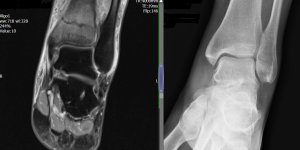

Undisplaced Fracture – Distal Tibial Metaphysis | Cases

Published on Jun 9, 2020

Female, 45. Started running 4 months ago. Gradually building distance. 3 week ago developed significant ankle swelling, pain and difficulty weight bearing after an 8 mile run. No history of injury X-ray – NAD Exam Ankle swollen Tender on palpation over left medial malleolus and along tibial shaft. MRI Coronal Saggital T1 There is an undisplaced [...] Read more